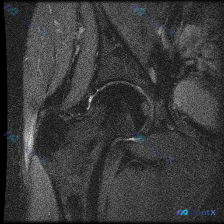

病例影像分析分享 今天整理了一例踝关节MRI的分析思路,原始提示看到「软组织积液」,我们一步步来拆解: 病例影像基本信息 这是一例踝关节MRI冠状位T2加权像,我们先做系统性解剖评估: 1. 骨与关节:胫距关节、距下关节间隙正常,关节面平滑,胫骨远端、距骨、跟骨骨髓信号均匀,没有骨赘、软骨下囊肿、骨...